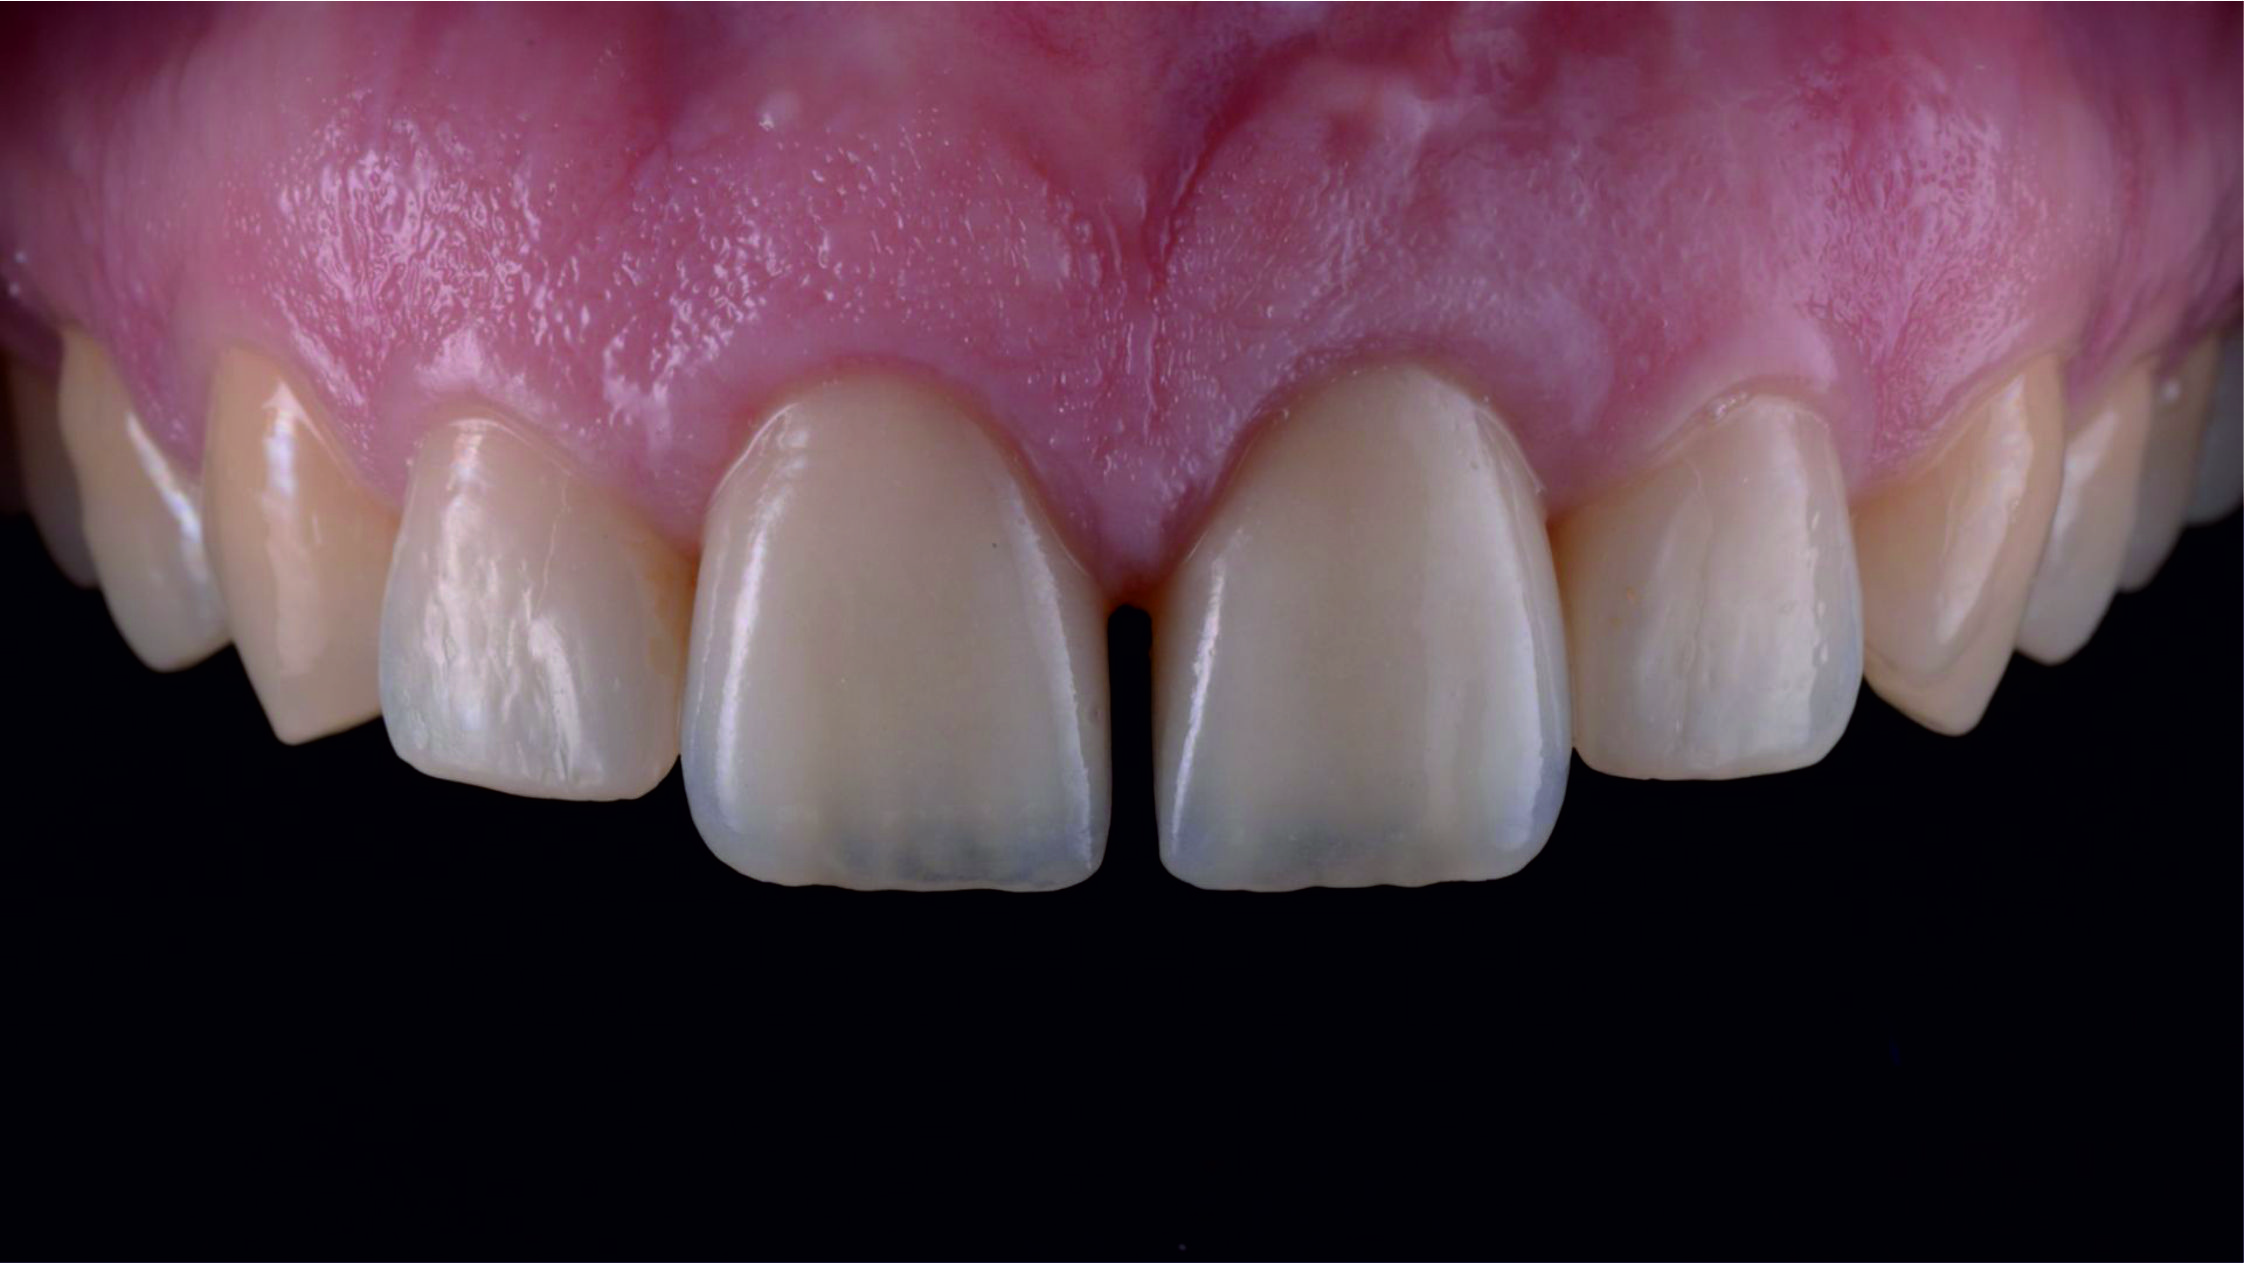

Фото 3. Внутрішньоротовий вигляд початкової ситуації.

Фото 4. Перед тим, як приступити до планування майбутнього естетичного вигляду зубів, необхідно переконатися в тому, що тканини пародонта здорові. Так ми зможемо встановити фактичне розташування рівня зенітів центральних різців.